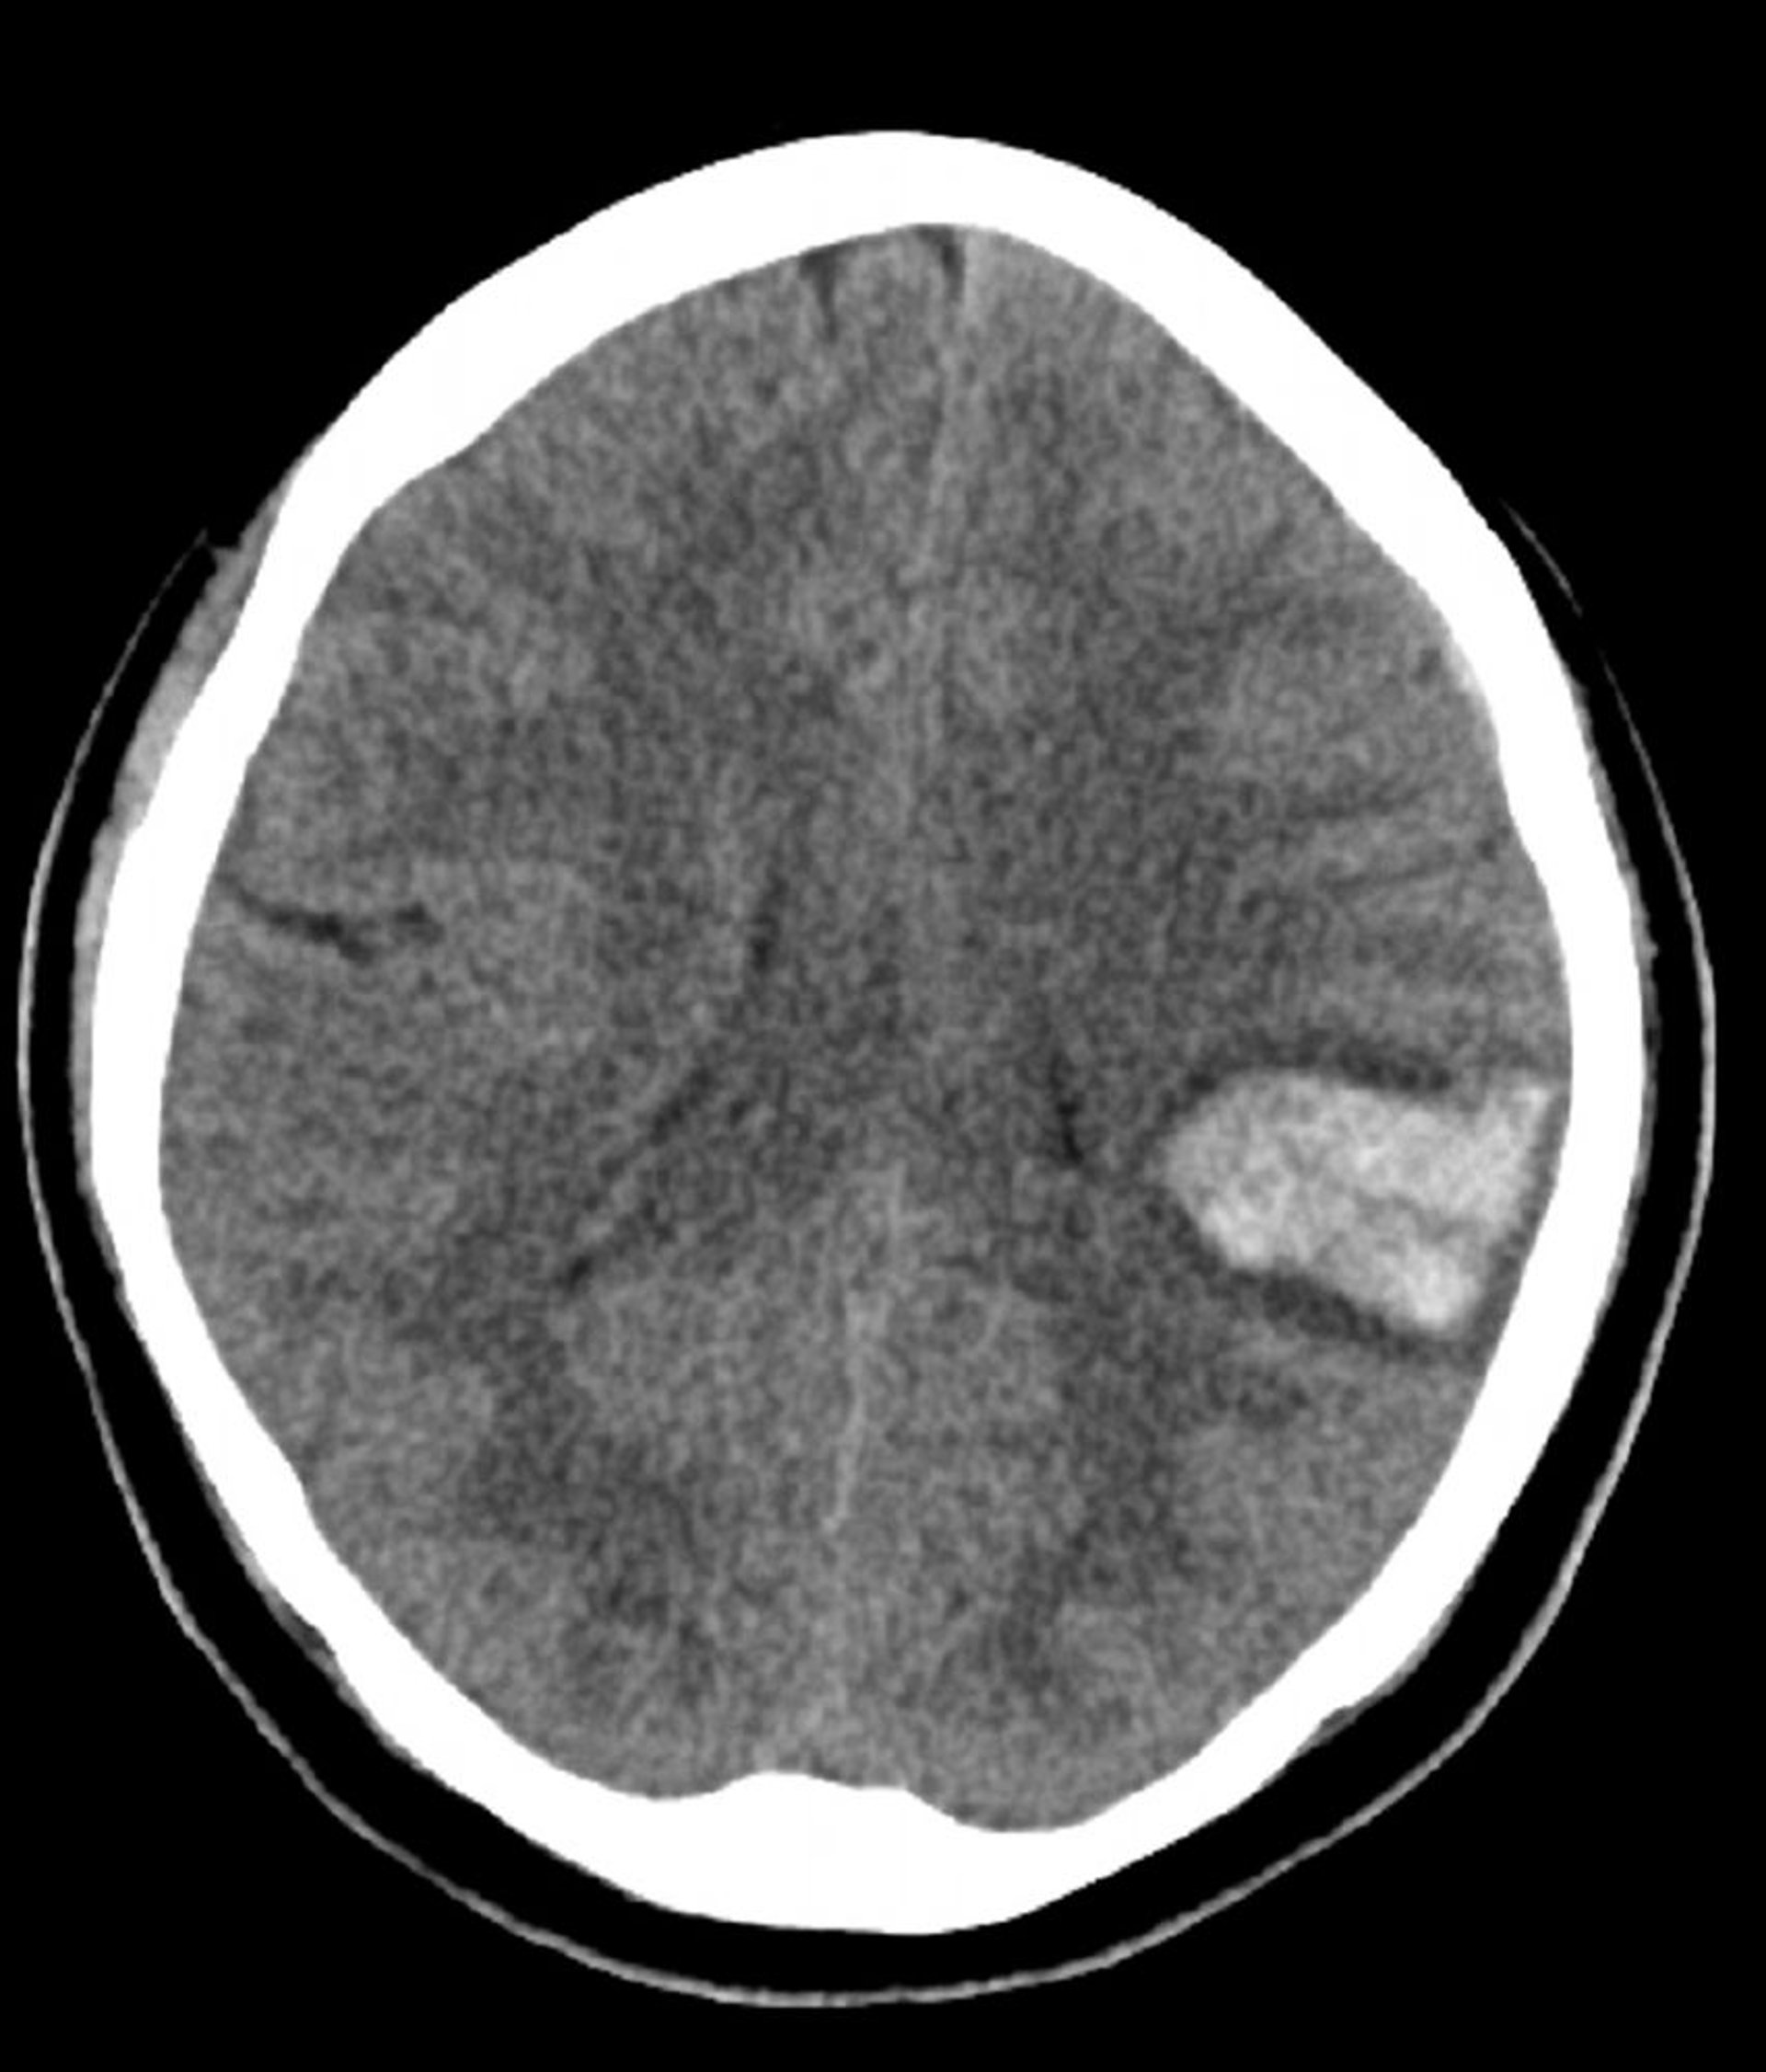

Intracerebral Hemorrhage

Increased density in the left brain seen on this noncontrast CT is consistent with intracerebral hemorrhage.